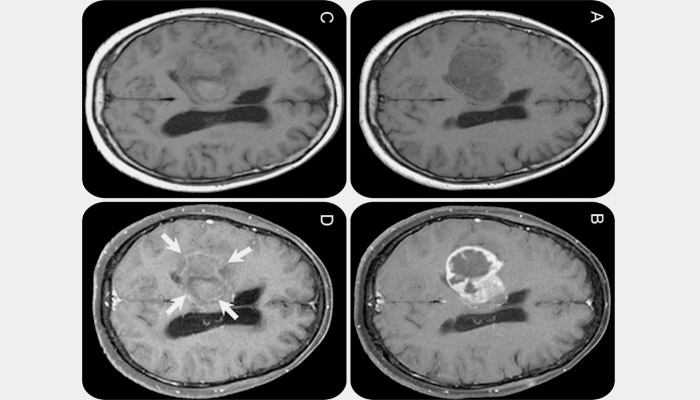

Коли пухлина швидко розростається, не має чітких меж, проникає у сусідні тканини, вона носить злоякісний характер. Виникає некроз тканин, кровотечі, часто це неоперабельний рак. Хворий може померти за кілька місяців. Більшість первинних злоякісних пухлин – гліоми – можуть мати різні ступені розвитку. Саме швидко і небезпечне новоутворення – глиобластома останньої 4 стадії розвитку. Так вона виглядає на фото.